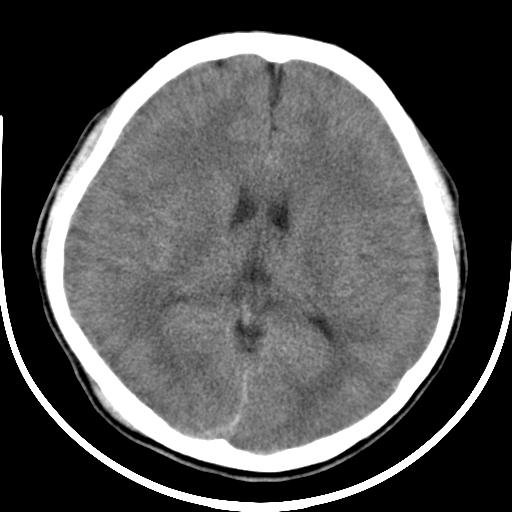

标题: CT16648:男19岁,头外伤后一小时,骨床未见骨折征象。 [打印本页]

标题: CT16648:男19岁,头外伤后一小时,骨床未见骨折征象。

颅内积气,右侧枕顶部头皮损伤.建议上传骨窗(如未见骨折,可加照头颅正侧位片及颅底hrct).

灰白质分界不清,侧脑室变小。考虑弥漫性脑水肿。

颅内积气,建议薄层重建寻找颅骨骨折.

颅内积气,应该就有骨折!。

颅内积气肯定有骨折,这点不用怀疑。

正好一个环状伪影重叠在皮质上,还以为是双侧硬膜下血肿呢,看了半天。

支持气颅,有可能存大乳突或颅底骨折,进一步检查。

颅内积气肯定有骨折,这点不用怀疑。有可能存大乳突或颅底骨折,但很多时候找不到骨折线

应该是合并了颅底骨折了,ct横段面不一定看的到的

右侧颞骨乳突部肯定有骨折,好好找找吧

颅内积气,少量蛛网膜下腔出血.